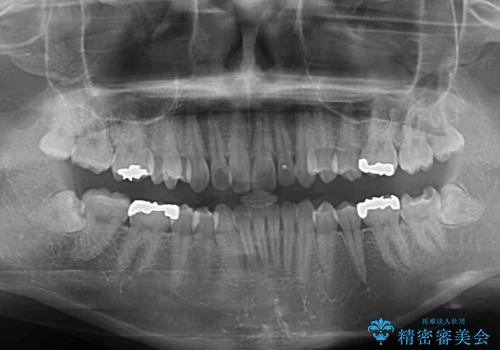

- 奥歯の虫歯と前歯のデコボコや突出感を気にして来院された患者様です。

上顎歯列が、下顎に対して前方にありましたが、口元に出っ歯の印象がなかったため、親知らずを抜歯した上で、上顎歯列全体を後方に移動させることとしました。

咬合力が強いため、アンカースクリューを使用し、ワイヤー装置にて矯正治療を行うこととしました。

矯正治療後は、奥歯の虫歯や銀歯を補綴・修復治療することとしました。